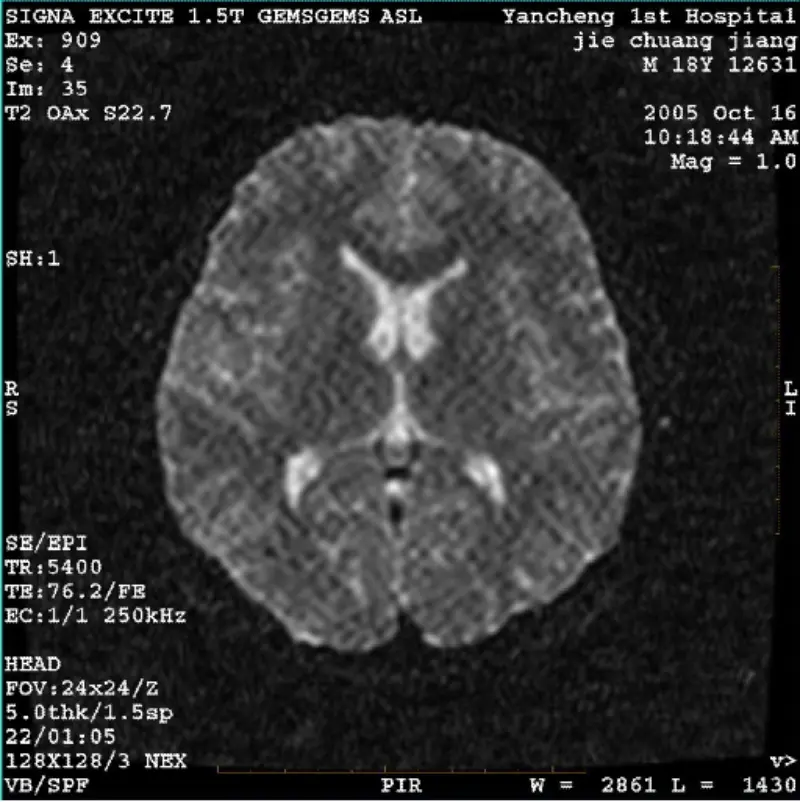

और पढ़ेंसिस्टम: 1.5T सिग्ना ट्विन एक्साइट II (सॉफ्टवेयर संस्करण 11.0M4) समस्या/लक्षण DWI (ज़ूम मोड और संपूर्ण मोड) और फ़िएस्टा (ज़ूम मोड और संपूर्ण मोड) छवि होना बॉडी कॉइल या हेड का उपयोग करते समय दृश्यमान रेटिकुलेट या कॉरडरॉय आर्टिफैक्ट से कोई फर्क नहीं पड़ता कुंडल, अन्य नियमित छवि सामान्य लगती है